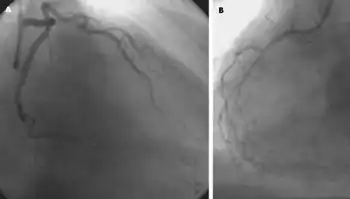

The drug is also commonly used in the hospital setting as a pharmacologic stress testing agent to identify coronary artery disease.